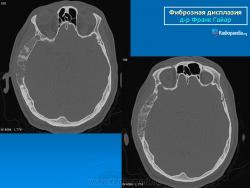

Локализация: для монооссальной фиброзной дисплазии характерно поражение одной из костей лицевого черепа, а также бедренной или большеберцовой кости, реже одного ребра; при полиоссальной фиброзной дисплазии страдают в первую очередь бедренная, большеберцовая и тазовые кости, не исключено и поражение мелких костей стопы, черепа, реже ребер. Рентгенологическая картина фиброзной дисплазии разнообразна. Патологические участки могут быть то более плотными, то более прозрачными по сравнению с окружающей костью, иногда имеют вид «матового стекла». Одни очаги четко отграничены зоной склероза, контуры других расплывчатые, что особенно характерно для костей черепа. Нередко выявляются узуры в кортикальном слое, а при наличии перелома — отчетливая периостальная реакция. При макроскопическом исследовании определяются беловато-красные опухолевые очаги разной плотности, в зависимости от степени выраженности их минерализации. Имеются многочисленные кисты, заполненные желтоватой или красноватой жидкостью, и полупрозрачные участки хряща до 3 см в диаметре.

Для фиброзной остеодисплазии, или болезни Брайцева-Лихтенштейна, характерно нарушение костеобразующей функции мезенхимы, проявляющееся в одной или нескольких костях, что ведет к их деформации и образованию в них очагов разрежения, обычно отграниченных от здоровой ткани кости склеротической каймой. Объем пораженной кости при этом может быть увеличен. Чаще поражаются трубчатые кости, но характерные изменения могут отмечаться и в костях черепа. В таких случаях возможны облитерация придаточных полостей носа, деформация глазниц, сужение отверстий в основании мозгового черепа и в лицевом черепе, ведущее к нарушению функции проходящих через них нервов и сосудов. Заболевание, возможно, наследственное, проявляется с детских лет. Описал в I927 г. отечественный хирург В.Р. Брайцев (1878-1964), несколько позже - американский патологоанатом L. Lichtenstein (1906-1977).